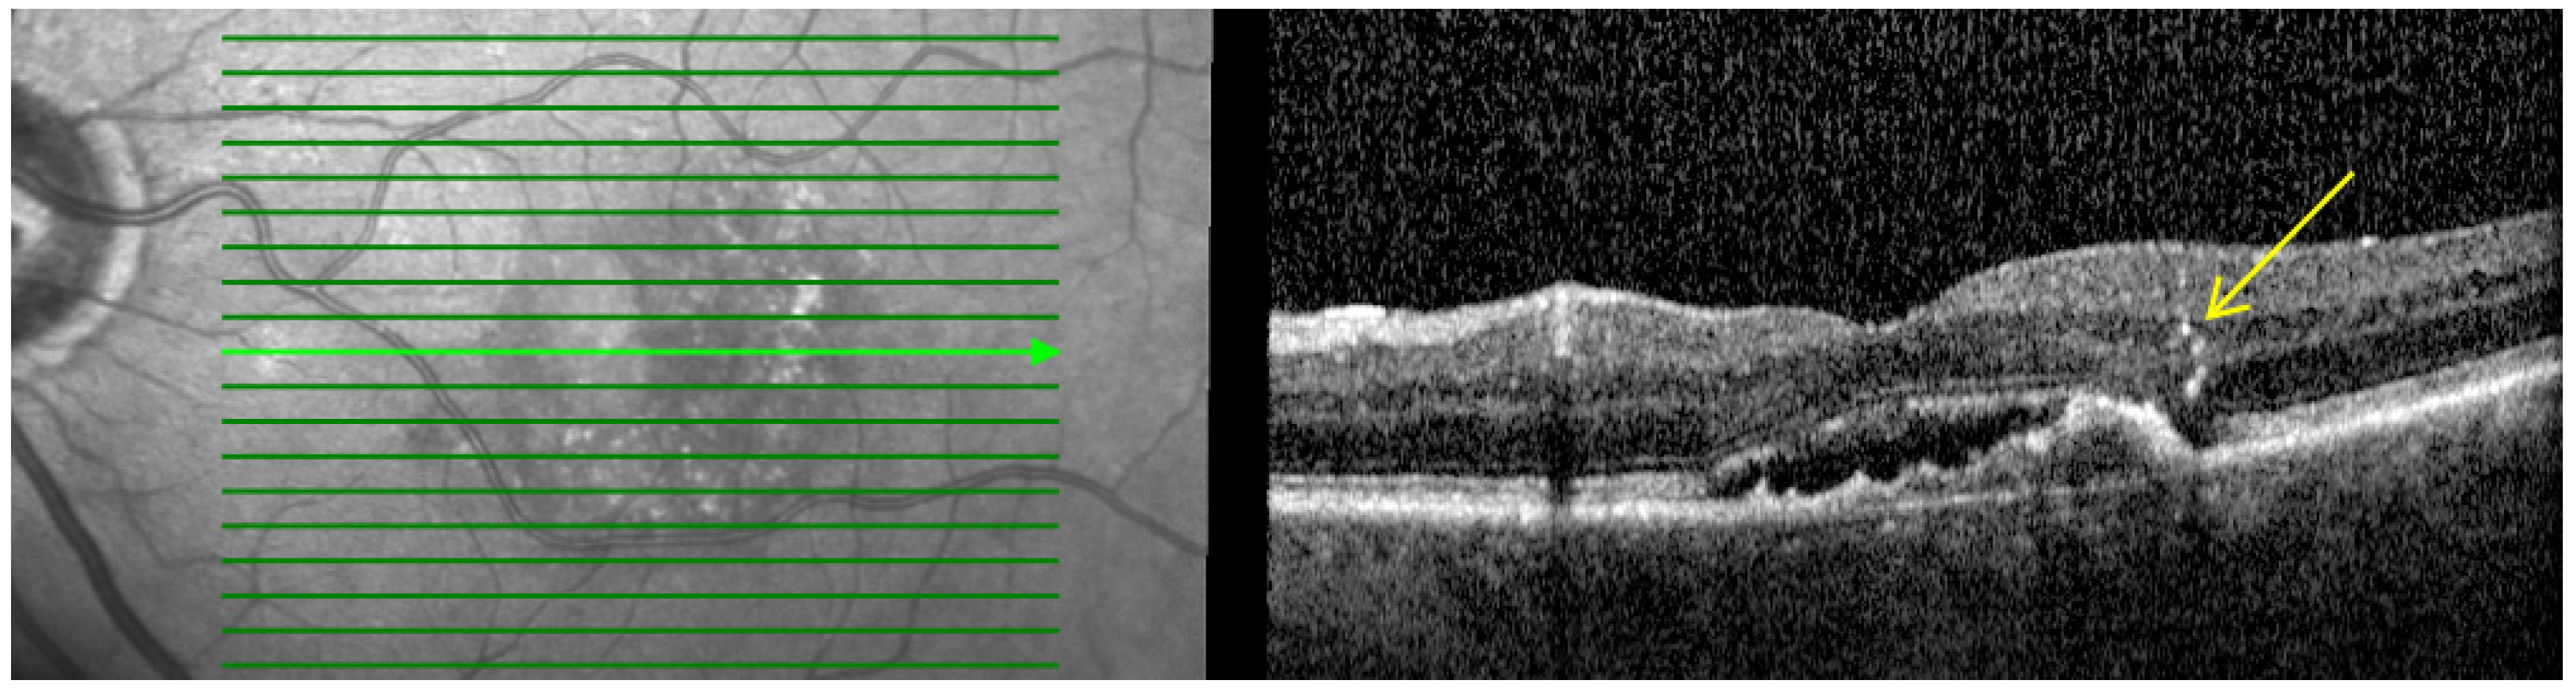

- Hyperreflective dots (HRDs): Defined as small, well-circumscribed lesions with a reflectivity equal to or greater than the RPE as shown in Figure 2. These lesions often occur over drusen and are associated with delays in visual acuity. It is hypothesized that reduced oxygen supply promotes anterior migration of RPE cells, which manifests as HRDs. On the other hand, HRDs in nAMD are also thought to be microglia, common immune cells in the inner retina that migrate from the inner retina to the outer retina when activated in an environment associated with degeneration [27,28].